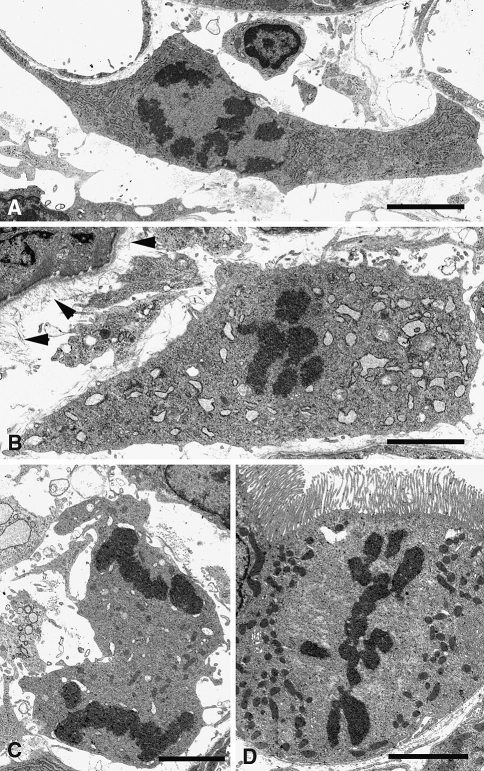

Fig. 13.

Mitotic figures in ureter-ligated kidneys on day 2; 80 nm epon sections. The fibroblast in a (prophase) displays a rather normal morphology with its close association with a capillary (upper left corner); the RER appears abnormally abundant but the shape of the cisterns is not altered. The fibroblasts in b shows inflated cisterns of RER. Note the abundance of collagen fibrils along the basement membrane of the tubule (arrowheads, compare with Fig. 9). The mononuclear cell in c cannot be precisely identified. d Proximal tubular cell. Bars 4 μm. Bars ~100 μm and 10 μm

Proliferation of interstitial cells

Mitoses in interstitial cells are rarely encountered in control kidneys. Thus, the occurrence of numerous mitoses within the interstitial space after ureteral ligature was particularly striking. All stages of mitoses were found in the light- (Fig. 1) and electron microscope (Fig. 13) and by immunofluorescence (Fig. 14) in all types of interstitial cells. Immunostaining for phospho-S-kinase, which is up regulated in the cytoplasm in all stages of mitosis (Fig. 14c), was helpful for easy spotting of mitoses at low magnification (Schmidt et al. 2007).

Quantitative analysis of mitotic interstitial cells in 1 μm epon sections showed a sharp increase of the mitotic index in the peritubular interstitium on day 2 in UUO (Fig. 15a). Thereafter the mitotic index decreased but it remained significantly higher in the occluded kidney at days 3 and 4 than in controls. Even though up to 20% of mitotic cells could not be identified it was evident that fibroblasts and mononuclear cells contributed similarly to the increase. This was confirmed by electron microscopy (Fig. 13), since of a total of 32 mitotic cells found on days 2, 3 and 4 in the interstitium, 17 were fibroblasts and 15 mononuclear cells.

In the electron microscope mitotic figures were seen in fibroblasts with normal RER as well as in fibroblasts with inflated RER (Fig. 13). In fluorescence microscopy mitotic figures in fibroblasts were independent of the levels of expression of 5’NT and αSMA (Fig. 14). Thus, cell proliferation affected the various stages of transformation of fibroblasts in myofibroblasts.